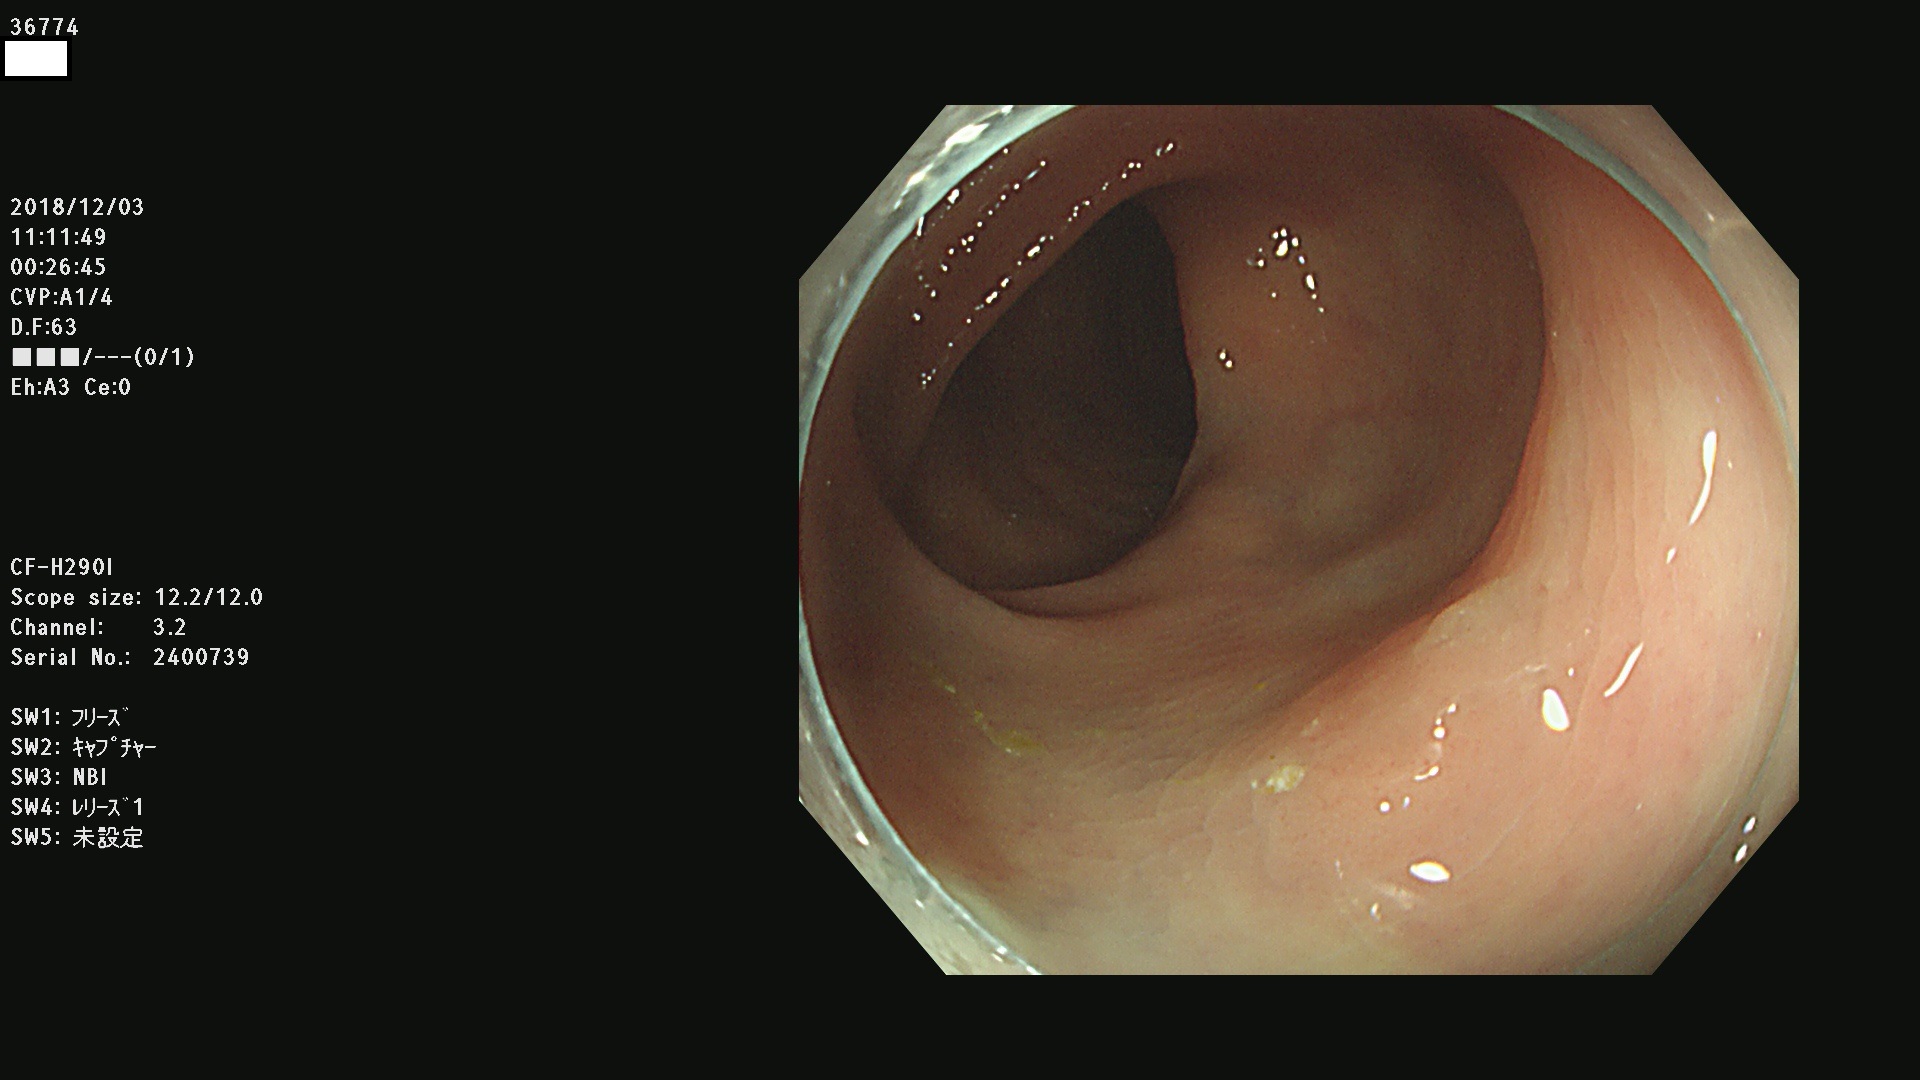

発見困難で危険性の高い平坦型病変(上記100名より抽出)